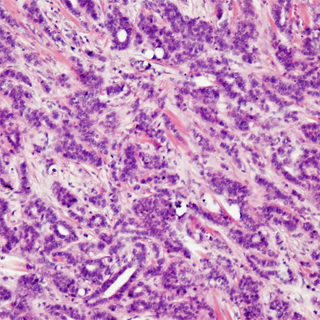

Pathologie

Egal wie verdächtig ein Tastbefund auch sein mag,

selbst wenn die Bildgebung noch so problematisch wirkt.

Die Gewissheit schafft erst der Pathologe.

Und nicht nur das. Er legt das Fundament jeder Behandlung.